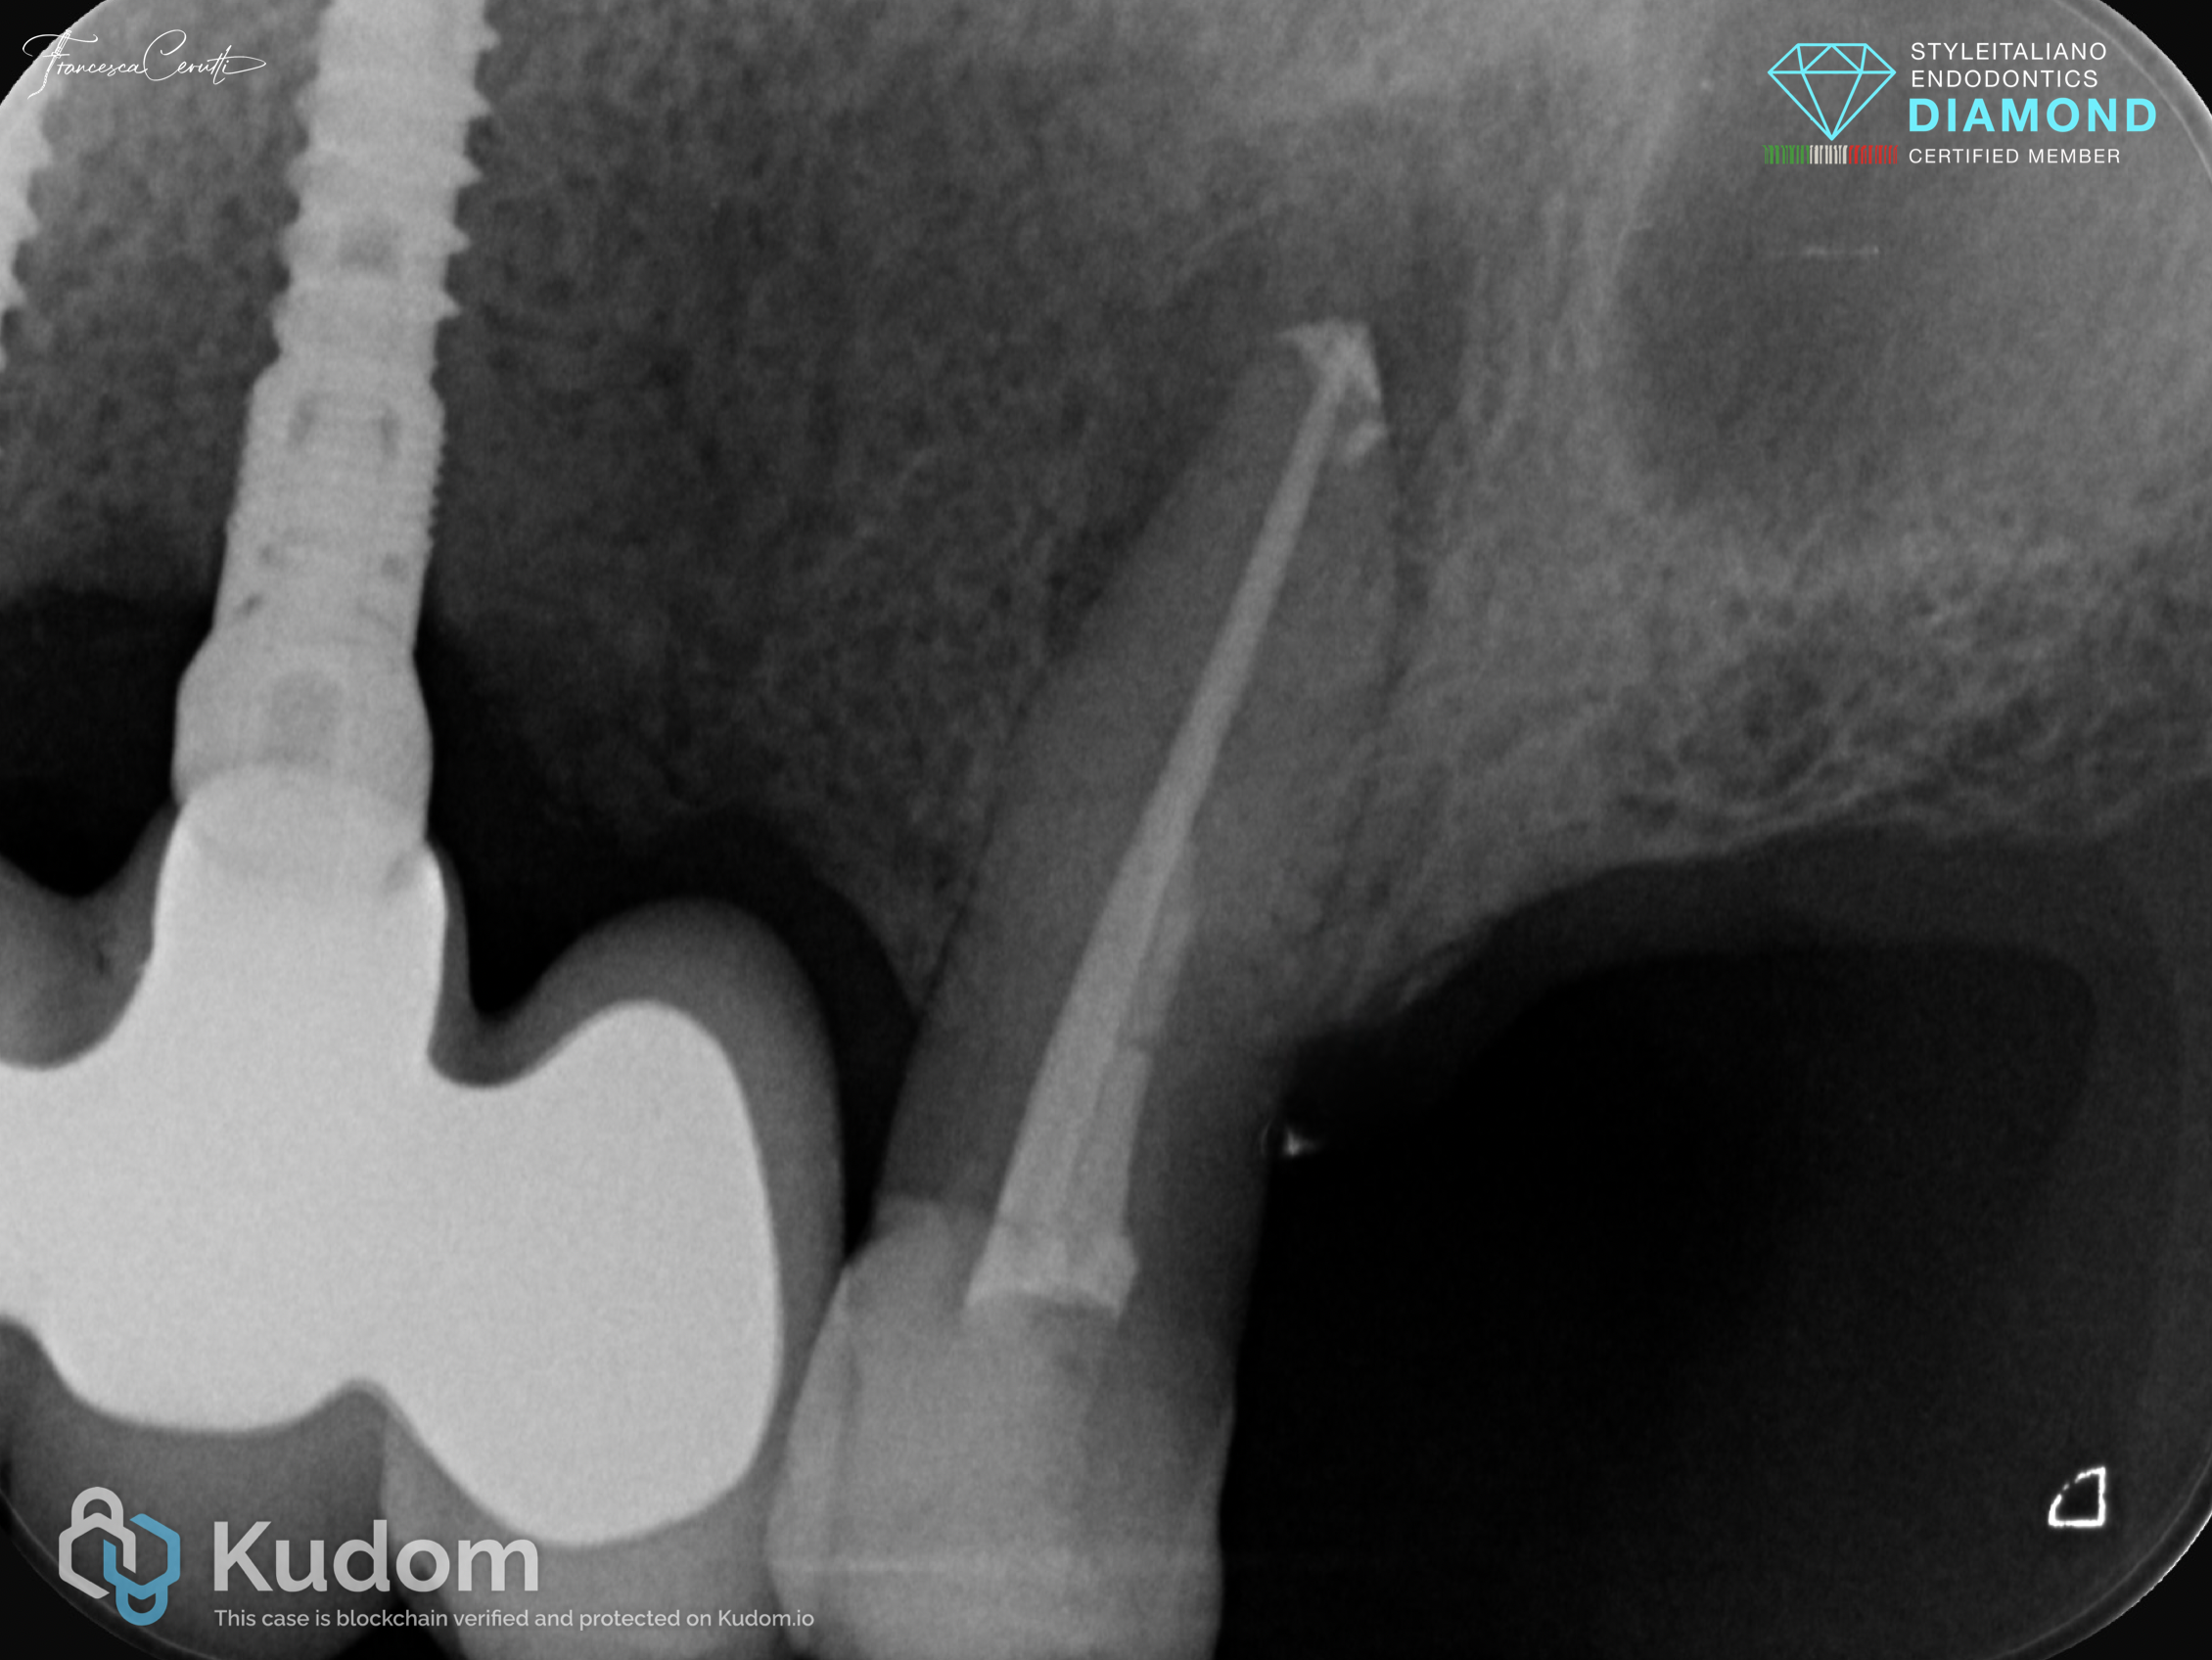

Fig. 2

Post operative X-ray.